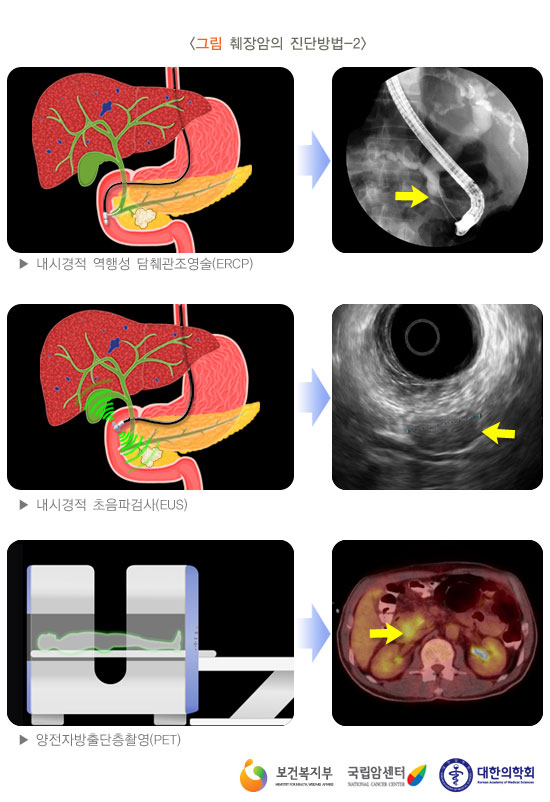

췌장암 검사방법

검사방법에 대하여 살펴보겠습니다. 최근에는 췌장암 검사에 내시경 초음파 검사가 많이 분비되기도 합니다 진단에 정확도가 아주 높으면서 조직검사도 또한 시행이 가능하다고 하더라고요. 췌장 종양과 만성 췌장염의 감별도 가능하고 정도가 작은 종양 진단도 내시경 초음파 검사가 가능하다고 하더라고요. 췌장암 초기증상을 보이는 경우 병원을 내방하면 CT복부 촬영을 통해 확인을 합니다. 가장 간단하고 판별이 가능한 검사방법이라고 합니다. 물론 초음파 검사를 미리감치 할 경우도 있겠으나 초음파 검사는 검사하는 분들의 재능에 따라 판단이 큽니다. CT복부 촬영으로 판단이 힘든 경우에는 MRI 검사가 시행이 되는 기질이 있어요. MRI눈 췌관, 담관도 관찰이 가능해서 간 전이도 확인이 되는 검사 합니다.